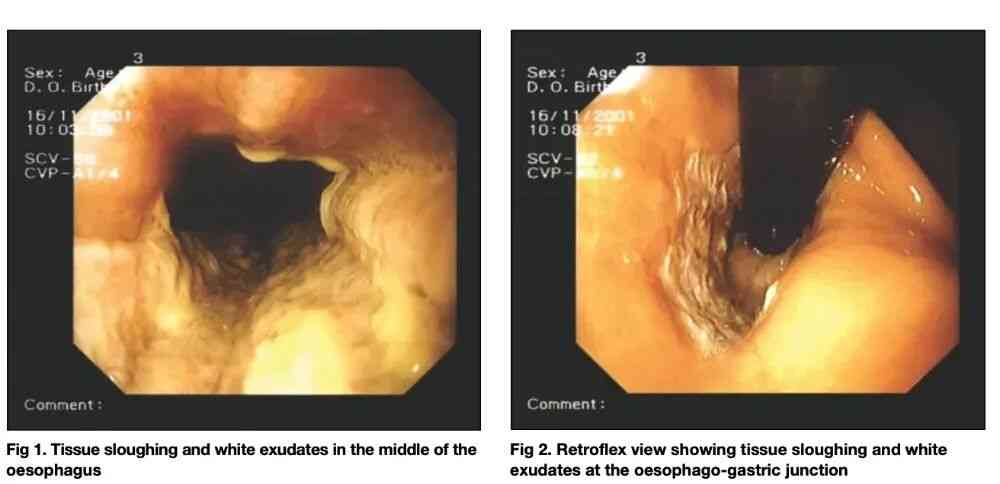

另一个广泛流传的方法,是喝醋软化鱼刺。但医学证据恰恰相反。一项病例报告显示,饮用普通食用醋不仅不能溶解鱼刺,反而可能造成口咽和食管的腐蚀性损伤[4]。这类损伤在内镜下表现为明确的黏膜炎症甚至溃疡,而鱼刺往往并未因此消失。